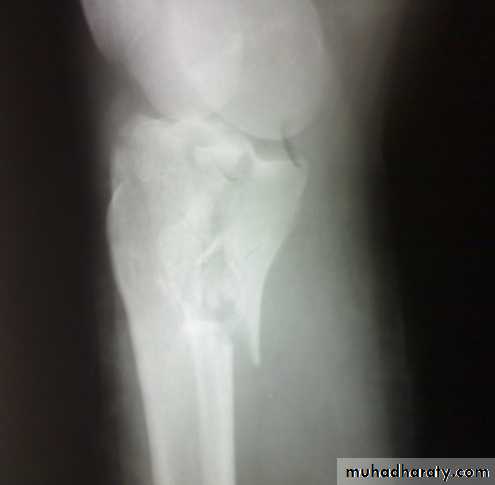

Tibial plateau fractures

Mechanism: medial or lateral bending force with axial loads, e.g. bumper fracture.

Doughy swelling of hemarthrosis.

Diffuse tenderness.

May be associated with knee ligament injury (collateral ligament, cruciate ligament).

X-ray:

One or both condyles may fracture with varying degrees of comminution.

C-T:

scan in complex fractures.